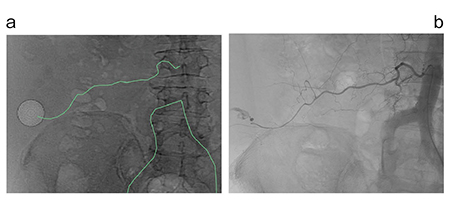

仮想透視画像がどのようなものか、実際の症例を提示する。図1は、転倒して右側腹部を打撲して出血した症例で、図1aがCTのボリュームデータからZiostation2で作成した仮想透視画像である。Extravasationの位置を丸く示し、責任血管の走行をライン(パス)で表しており、実際のX線透視画像(図1b)とよく似ている。この画像から責任血管の起始部はL3棘突起上縁の2mm外側にあることがわかり、手技の際にはピンポイントでねらってカテーテル操作が可能になる。この症例で手技を担当したのはカテ経験1年弱の救急医だったが、血管を4秒程度で選択できた。仮想透視画像では、術前に透視と同様の画像で血管走行を確認でき、スムーズな手技が可能になる。以下に、仮想透視画像による症例を提示する。

図1 仮想透視画像(Virtual Fluoroscopic Image)

a:仮想透視画像 b:実際のX線透視画像